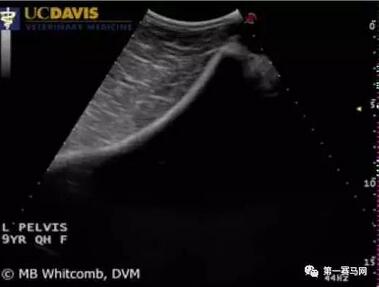

不清楚大家是否记得香港新晋四岁马系列赛三冠王“佳龙驹”。 香港上阵13次,拿下8场头马,累积总奖金超过3000万港元,香港首匹四岁马三冠王。 然而在本月7日香港一场国际一级赛“冠军一哩赛”中,“佳龙驹”骨盆发生严重骨折。根据香港马会兽医事务主管李恪城医生表示:“佳龙驹”还不幸地出现严重的并发症。 ▲第 7 场 - 冠军一哩赛 “佳龙驹”跑到半程骑师紧急收停 骨盆骨折 Pelvis Fractures (注意:“下划线”处在文章下方有注释哦!) -------------------------------------------- 马骨盆骨折常发于直接的外力损伤(如摔倒,踢伤),或者应力性骨折。 而赛马最常发见发生应力性骨折。 -------------------------------------------- 症状: 骨盆骨折的马可能会表现出跛行、不愿意走动、不舒服、从马后方视诊发现臀部肌肉或骨骼突出部两侧不对称等。 发病较久的骨折可导致臀肌萎缩。 直肠检查可能察觉到捻发音或骨盆腔形状变化,但捻发音比较难察觉到。 根据骨盆不同的骨折部位,有不同的表现。 例如髋臼骨折总是表现为严重的跛行,疼痛到甚至达无负重的状态。 再例如髋结节骨折才能看到外部肿胀,一般表现为突出部两侧不对称。 ▲马髋骨结构图:1 荐结节Tuber sacrale 2 髂嵴Crest of ilium 3 髋结节Tuber coxae 4 坐骨棘Ishiadic spine 5 髋臼Acetabulum 6 耻骨联合Symphysis pelvis 7坐骨结节Tuber ischii ▲马骨盆结构图,背侧面 -------------------------------------------- 诊断: 马站立状态下超声检查大多数能够确诊。 也可在站立的状态下拍摄骨盆的X线片,但需要大功率X线机和多方位摄片最终进行整合分析。 ▲超声检查:正常髂骨表面连续的高回声带(高亮区) ▲超声检查:髂骨表面断开的高回声,表明髂骨骨折 -------------------------------------------- 预后及治疗: 单纯的无移位性盆骨骨折一般能够在一年内得到满意康复,甚至能够恢复到骨折前的运动状态。 有研究表明超过75%的马匹在盆骨骨折恢复后能够继续比赛或者繁育的。少数马匹康复后仍有慢性跛行。 最好的治疗方法就是静养,让马匹待在厚垫料的马厩内保持安静状态,减少走动,持续6个月左右。 但髋臼骨折预后一般较其他骨盆骨折差,原因在于髋臼骨折容易导致移位和引起骨关节炎的发生。 唯一的治疗方法也是保持6到9个月的休息静养,针对骨关节炎进行对症治疗。 对于骨盆骨折的治疗一般很少采用外科手术的治疗方法,因为手术难度大,而且术后护理也是一大难题。 -------------------------------------------- 并发症: “佳龙驹”骨盆严重骨折后出现严重并发症,后决定“安乐”处理。而骨盆骨折的并发症一般以下几点: 1.出血性休克 2.腹膜后血肿 3.尿道或膀胱损伤 4.直肠损伤 5.神经损伤 高能 注释 1 骨盘:是由骶骨、尾骨和两块髋骨所组成。骶骨与髂骨和骶骨与尾骨间,均有坚强韧带支持连结,形成关节,一般不能活动。 髋骨:是由髂骨、坐骨及耻骨联合组成的不规则骨骼。 即骨盆是一个比较复杂的结果,而髋骨只是骨盆结构中的一部分。 2 应力性骨折:是一种过度使用造成的骨骼应力性骨折损伤,当肌肉过度使用疲劳后,不能及时吸收反复碰撞所产生的震动,将应力传导至骨骼,可引起小的骨裂或骨折。 速度赛马骨折最常发生应力性骨折。例如肱骨、胫骨、桡骨,骨盘骨等。 ▲选自香港赛马会出赛马匹伤患记录 3 预后:是指预测疾病的可能病程和结局。一般分为预后良好、预后不良、预后慎重和预后可疑。 相关阅读:【视频】将军难免阵上亡,香港新晋四岁马系列赛三冠王“佳龙驹”今天为马迷奉上最后一战 注:正文内容由小编整理而得,不妥之处请指出,谢谢! 本文来自第一赛马网,图片来源网站,转载请注明出处!